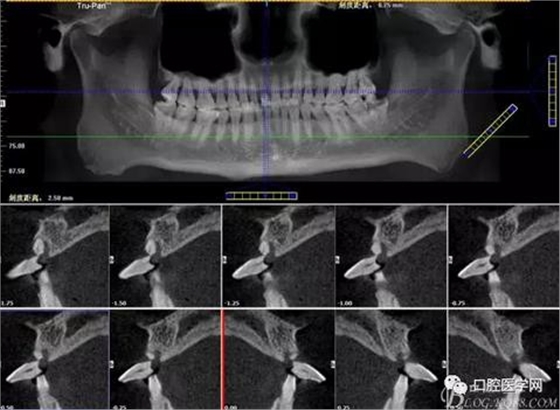

圖2 術前CT